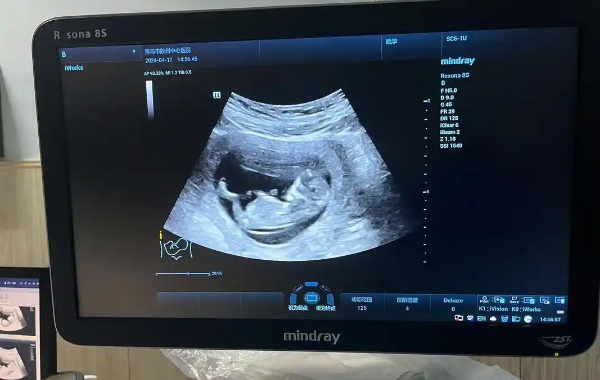

最近在孕妈群里总能看到这样的讨论:「昨天做NT看到宝宝的小鸡图了」「12周就能知道性别了吧?」。作为经历过两次产检的过来人,今天咱们就掰开揉碎了聊聊,这个让准爸妈们又期待又困惑的NT检查到底藏着哪些门道。一、NT检查的正确打开方式孕12周左右的NT检查全称「颈项透明层扫描」,说白了就是用B超测量胎儿脖子后面的液体厚度。这个数值要是超过2.5毫米,医生就会建议做进一步检查。北京妇产医院2022年的数